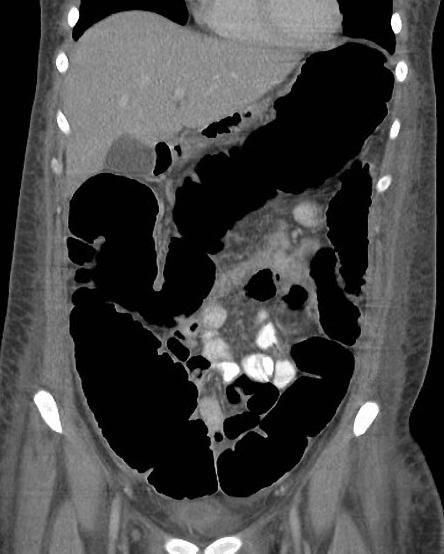

Toxic megacolon dans

maladie de Crohn . Image de distension du colon

transverse avec image de stenose inflamatoire et

epaissisement du colon sigmoigienne . Image

radiologique TDM en coupe coronale |

Meme cas en

coupe coronal a traver la colon transverse

. Maladie |